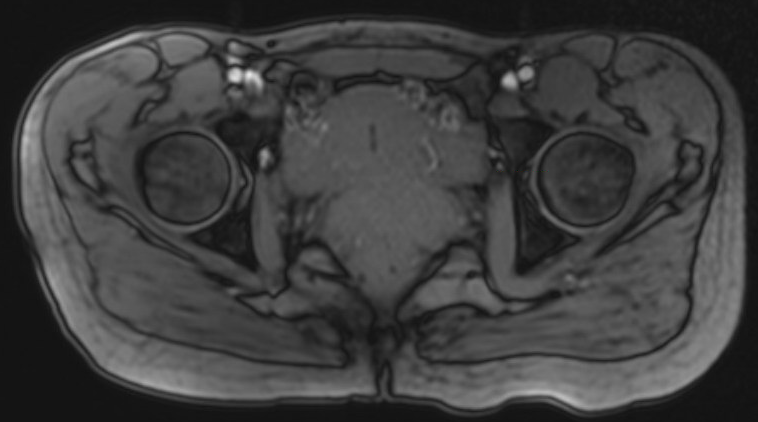

MRI

Labral tears

Best seen on coronal MRI